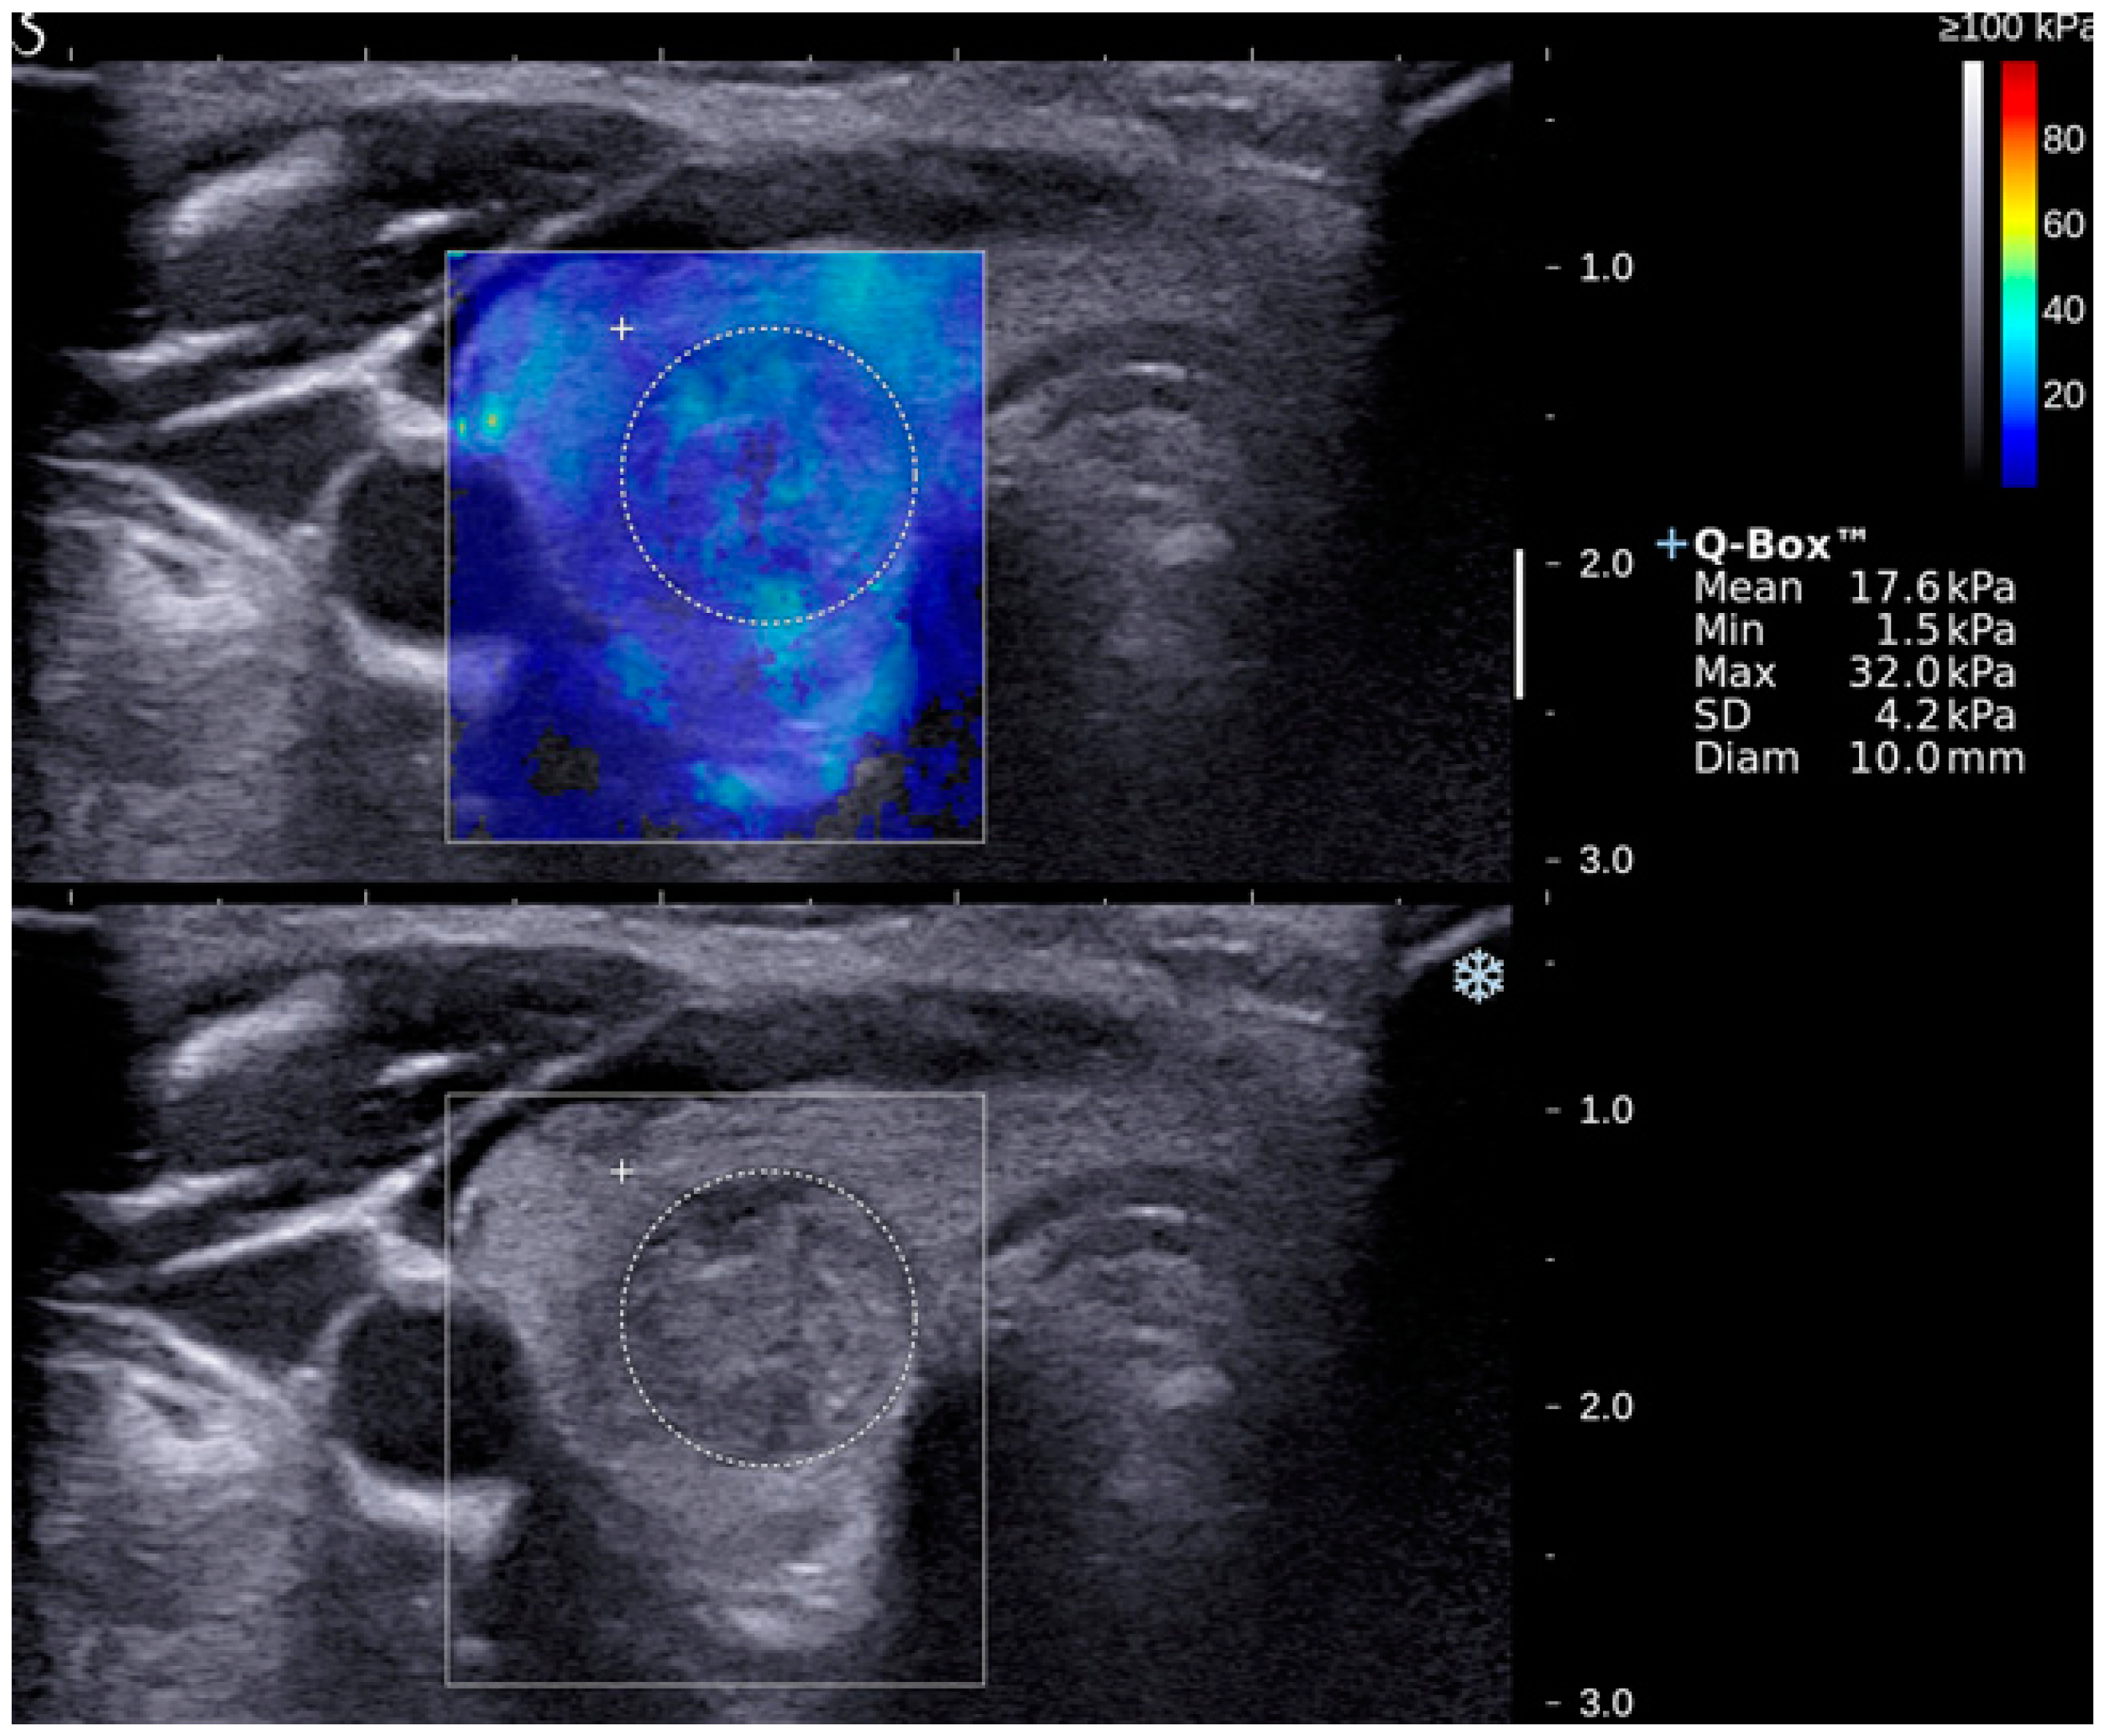

| Emax | 50.3 ± 3.1 | 85.2 ± 8.1 | <0.05 (50.9–63.5; 73.0–106.1) |

| Emean | 20.2 ± 1.0 | 26.6 ± 2.5 | <0.05 (19.5–23.5; 23.5–33.9) |